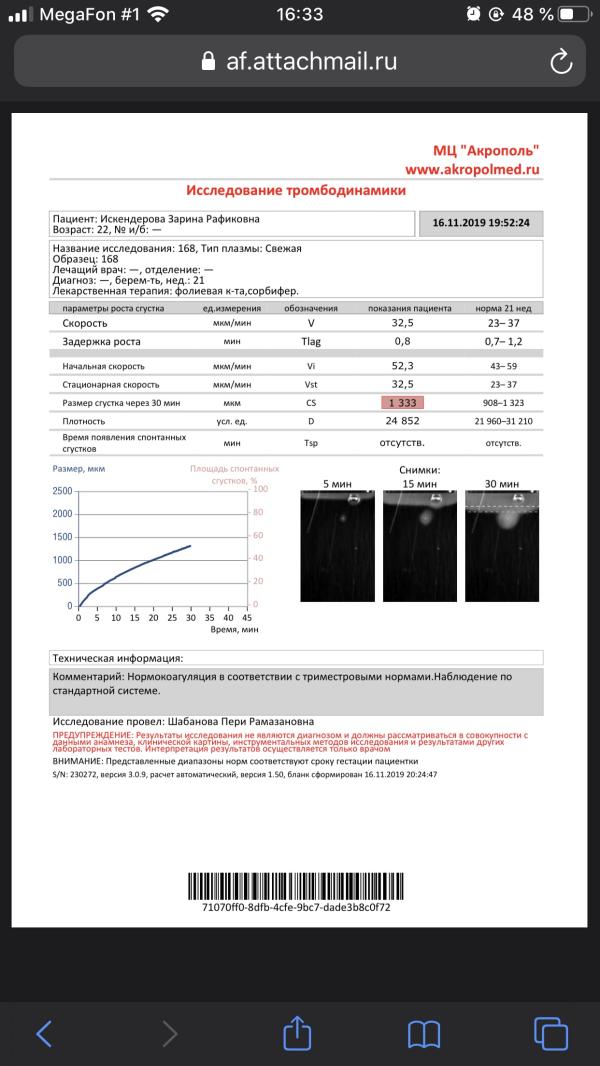

Кто разбирается ) сдавала кровь на тромбодинамику , все ли в норме?

Вроде все в норме 👍по крайней мере так написано . Говорили этот анализ только в здоровье и фемили делают